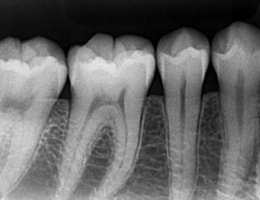

被曝量の少ない「デジタルレントゲン」を完備!

超高感度だから被曝量が軽減!子供さんにも優しいレントゲン!

デジタルレントゲンに使われているX線センサーは、デジタルならではの高感度!

照射時間が短縮され、より低線量でのレントゲン画像取得が可能となります。

当院のデジタルレントゲンは、

従来のフィルムを使用したレントゲン撮影に比べ、

人体に受ける放射線の量を、約1/4~1/10に抑える事が可能です。

現状を詳細に把握するため、小さいレントゲンを10枚撮って診断・治療をしております。

これにより歯石、歯周ポケット等も詳細に把握でき、緻密な治療を提供することが出来ます。